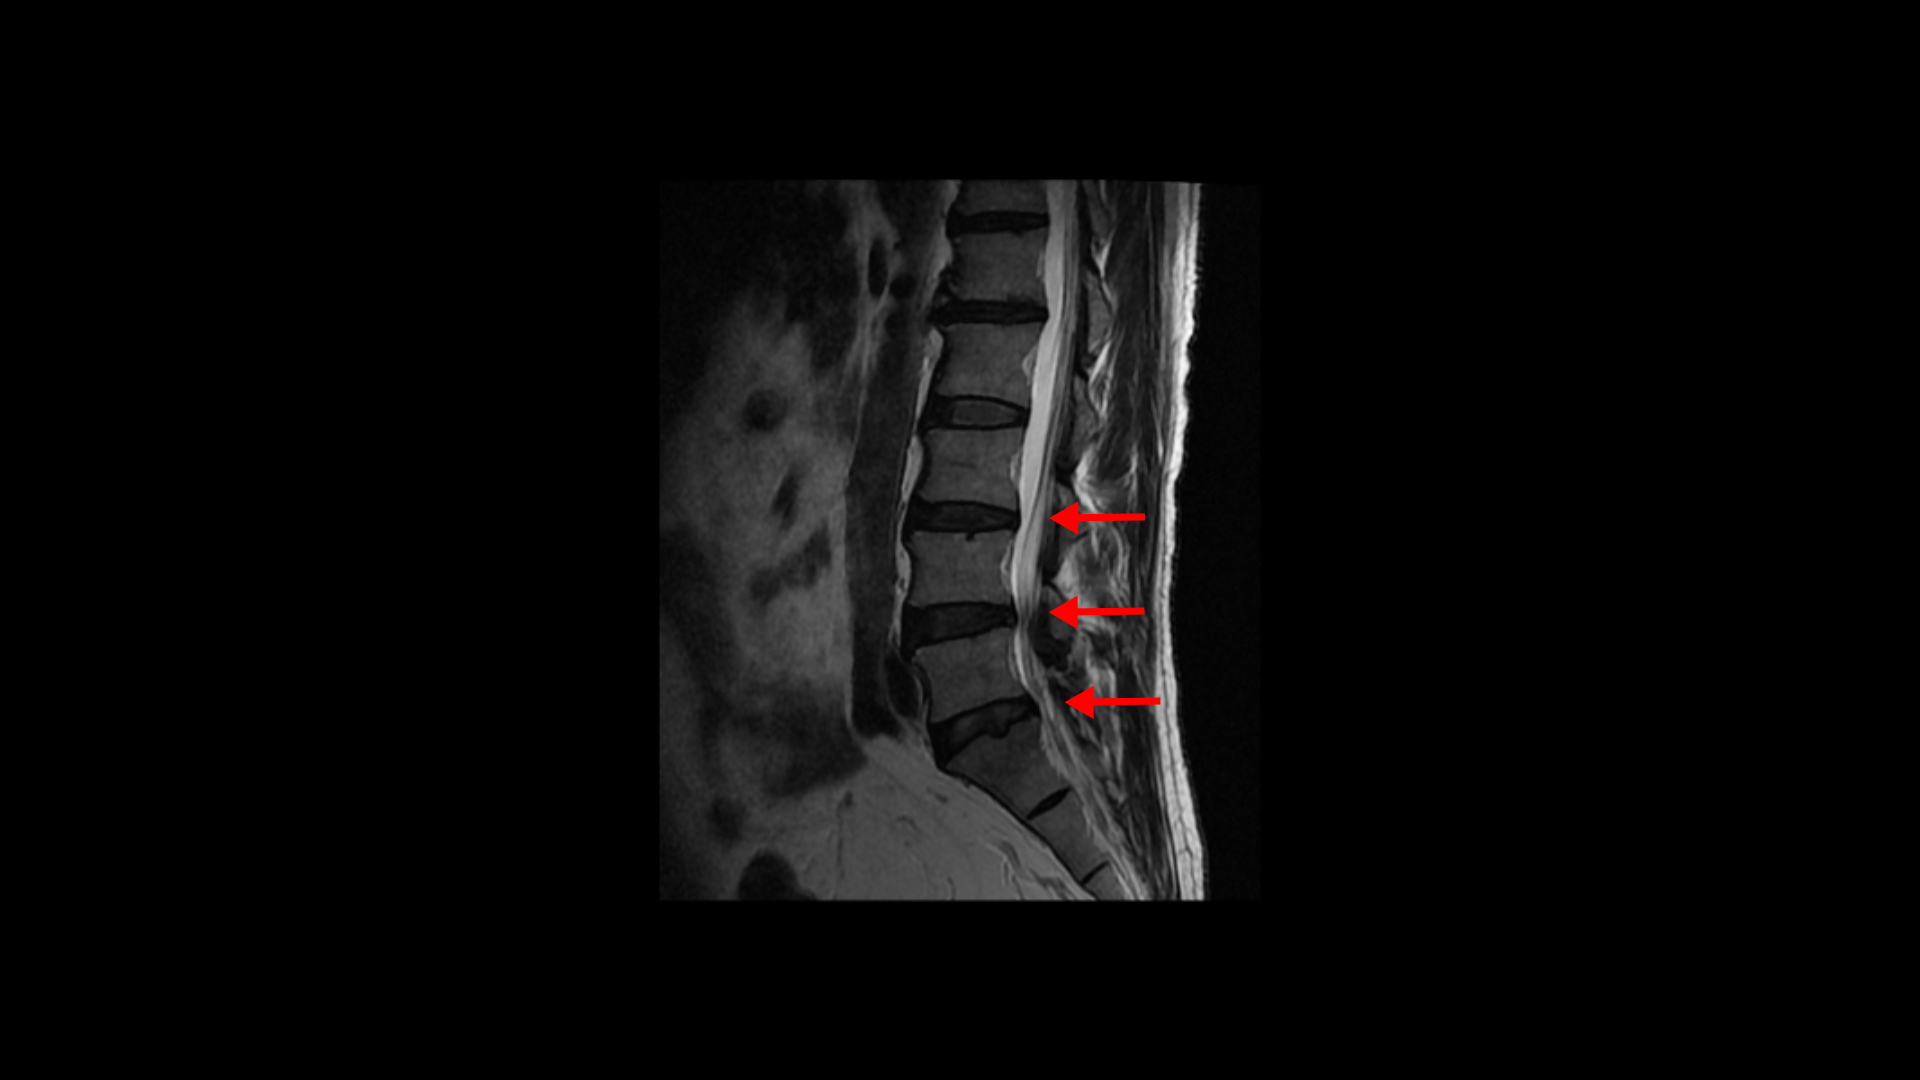

특히 MRI에서 보이는 신경 눌림이 심하지 않을수록 근육 문제일 가능성은 훨씬 더 높아집니다. 이 환자분 MRI를 한번 볼까요? 세 마디에 퇴행성 디스크가 있지만 심하지 않습니다.

4번 5번 마디의 척추관도 협착이 진행되었지만 좁아진 게 많이 심하지 않습니다.

오른쪽, 왼쪽 신경이 빠져나가는 추간공도 조금 좁아지긴 했지만 별로 심하지 않습니다.

이렇게 신경 구멍 좁아짐이 심하지 않으면 근육 문제일 가능성은 훨씬 높아집니다. 그리고 신경 구멍이 많이 좁아져 신경 눌림이 심해 보인다고 하더라도 역시 어느 날 갑자기 한쪽 다리, 엉덩이가 아픈 증상은 근육 문제가 가장 중요한 원인입니다.